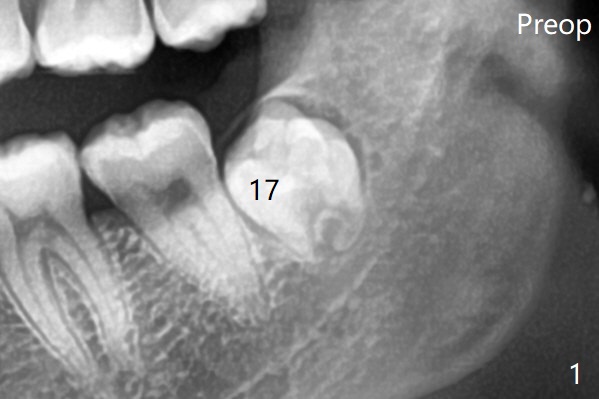

原来右下牙槽窝放置骨胶原塞(Osteogen Plug),而左下胶原塞。

塞的密度       Last     Next   智齿拔除